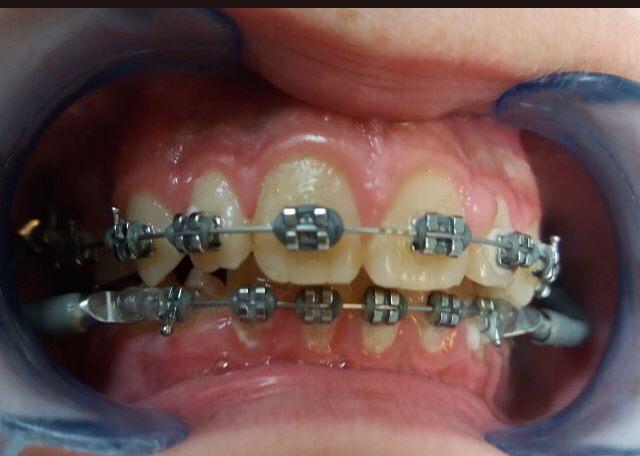

Vamos a ver el tratamiento de ortodoncia de un paciente de 11 años de edad en el que se observa una clase II de tipo dento-alveolar. Tiene un perfil de ligera protrusión del maxilar superior y retrusión de la mandíbula. Los incisivos inferiores llegan a contactar con el paladar superior pero muy hacia atrás. Esto le da un perfil de pájaro. Siendo la causa diversa en las que se mezcla diferentes parafunciones como interposición del labio inferior entre los dientes incisivos superiores e inferiores, o también interposición lingual al tragar etc. Es decir son los músculos (labio, lengua etc.) con sus malos hábitos los que producen las mal oclusiones e incluso trastornos del desarrollo óseo maxilomandibular normal. Es decir los músculos de la cara son los arquitectos de los huesos faciales, en este caso que exponemos para mal.

El tratamiento que se propone es alineamiento dental y estimular un desarrollo o crecimiento mandibular con algo que estimule dicho crecimiento. Este “algo” son los “aparatos funcionales” que actúan como si fueran poderosos músculos que tienden a empujar o estirar (según se diseñe) las estructuras dento-óseas de forma que estimula su crecimiento, siendo, que por su edad, está en época de máximo crecimiento. La mandíbula es un hueso capaz de crecer hasta los 25 años si se la estimula correctamente. Este aparato funcional es una especie de “jumper” o “saltador” o “empujador” que empuja el maxilar superior hacia atrás y empuja la mandíbula hacia delante aprovechando la fuerza de cierre de la arcada dental. Se lleva durante seis meses más o menos y el paciente no se lo puede quitar, es por esto que en realidad funciona tan rápido.

Recordamos que los músculos de la cara son los arquitectos de los huesos faciales, en este caso el aparato funcional, que es como un músculo, actúa para bien. Trascurrido este tiempo el paciente lleva elásticos de cierre para cerrar espacios dentales y resto de ajustes oclusales. Posteriormente a la retirada del aparato de ortodoncia el paciente lleva retenciones fijas y removibles durante la noche que garanticen el resultado en cuanto a recidivas.